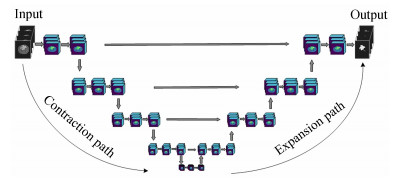

三维卷积神经网络:

若采用二维卷积神经网络进行特征提取,则无法充分利用三维MRI脑肿瘤数据,为高效利用病灶的立体三维信息,采用三维卷积神经网络进行特征提取.图 3为传统的二维卷积神经网络的结构示意图,主要由卷积层、池化层以及全连接层构成,可以看出网络处理的数据均为二维格式.

图 3 二维卷积神经网络结构示意图

三维卷积神经网络与二维卷积神经网络原理类似,不同之处在于:三维卷积神经网络是在三维数据上进行卷积操作,卷积核及网络数据输出的数据均为三维格式.三维卷积的示意图如图 4所示.